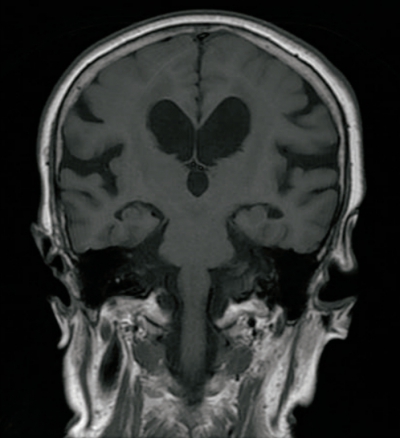

意識はJCSⅠ-2。体温 36.5 ℃。脈拍 86/分、整。血圧 142/88 mmHg。呼吸数 14/分。SpO₂ 97% (room air)。Mini-MentalState Examination〈MMSE〉23点(30点満点) 。頭部MRIのFLAIR水平断像及びT1強調冠状断像を別に示す。